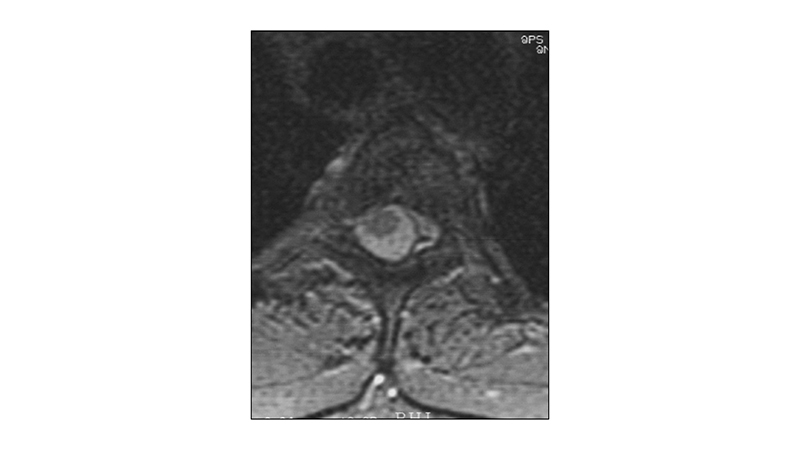

Εικόνα 2: Μαγνητική τομογραφία, με σκιαγραφικό, στο επίπεδο του Θ3 σπονδύλου: Το αιμαγγείωμα παρουσιάζει έντονη χαρακτηριστική πρόσληψη μετά τη χορήγηση σκαιγραφικού, με παρασπονδυλική επέκταση. Επεκτείνεται επίσης προς τα πίσω ενδοκαναλικά με παρεκτόπιση του μυελού και πλάγια προς τα πλάγια σπονδυλικά τρήματα κυρίως αριστερά, πιέζοντας την σύστοιχη νωτιαία ρίζα.

peristatiko aimaggeiwmatos spondulikhs sthlhs.002